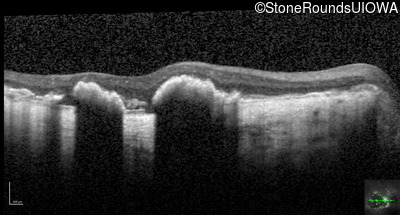

Optical Coherence Tomography - Right - Count Fingers 2'

Exemplar / OCT Stack

Optical Coherence Tomography - Left - Count Fingers 2'